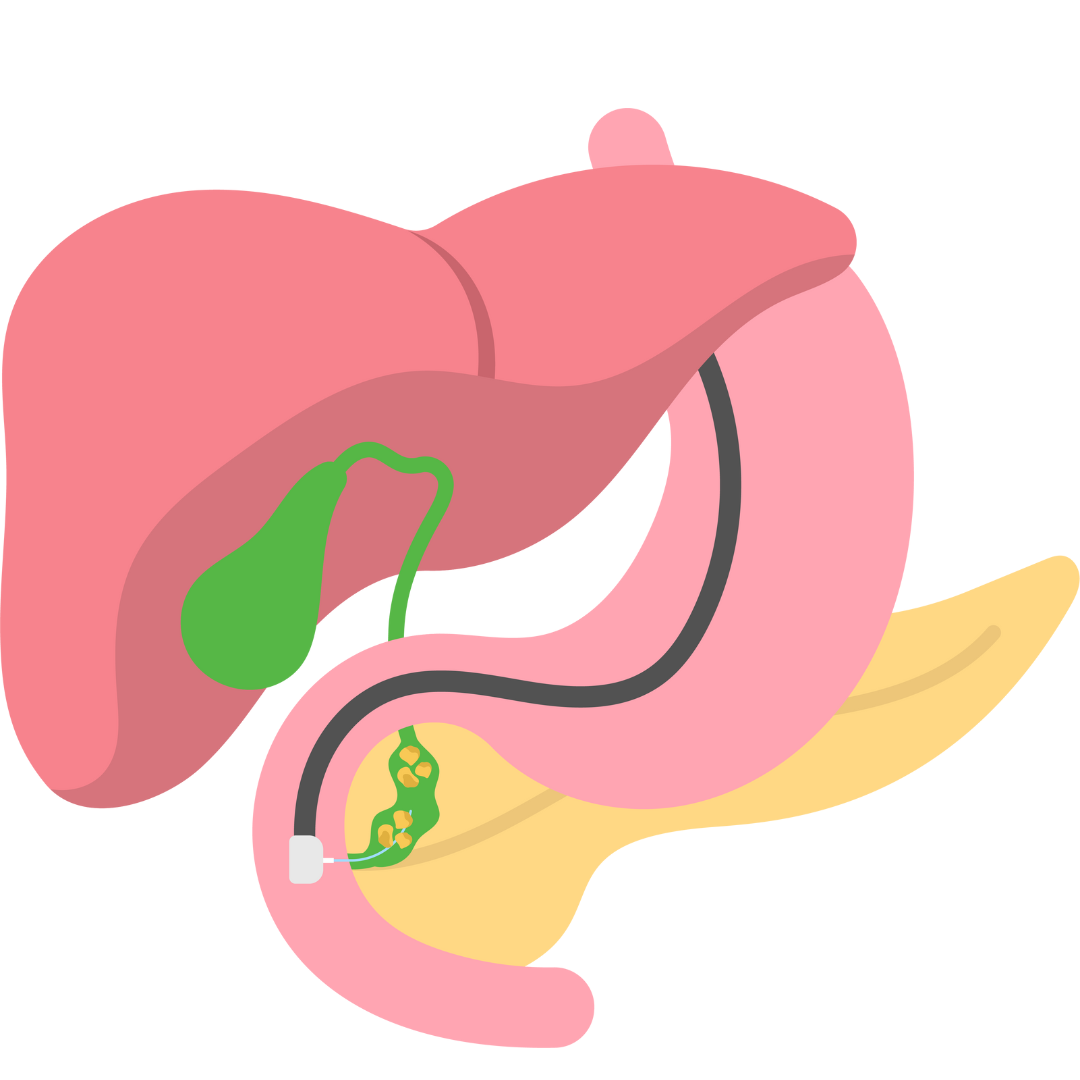

Brain Tumour

Our neurosurgeon specializes in the diagnosis and treatment of brain tumors, offering comprehensive care and personalized interventions to optimize neurological health and improve outcomes.

Spinal Tumour

Our neurosurgeon provides specialized care for spine tumors, offering comprehensive evaluations and treatments to optimize spinal health and improve overall well-being.

Neuro Vascular Surgery (AVM)

Our neurosurgeon specializes in neurovascular surgery, offering advanced interventions to treat vascular disorders, optimize blood flow, and improve overall neurological health.